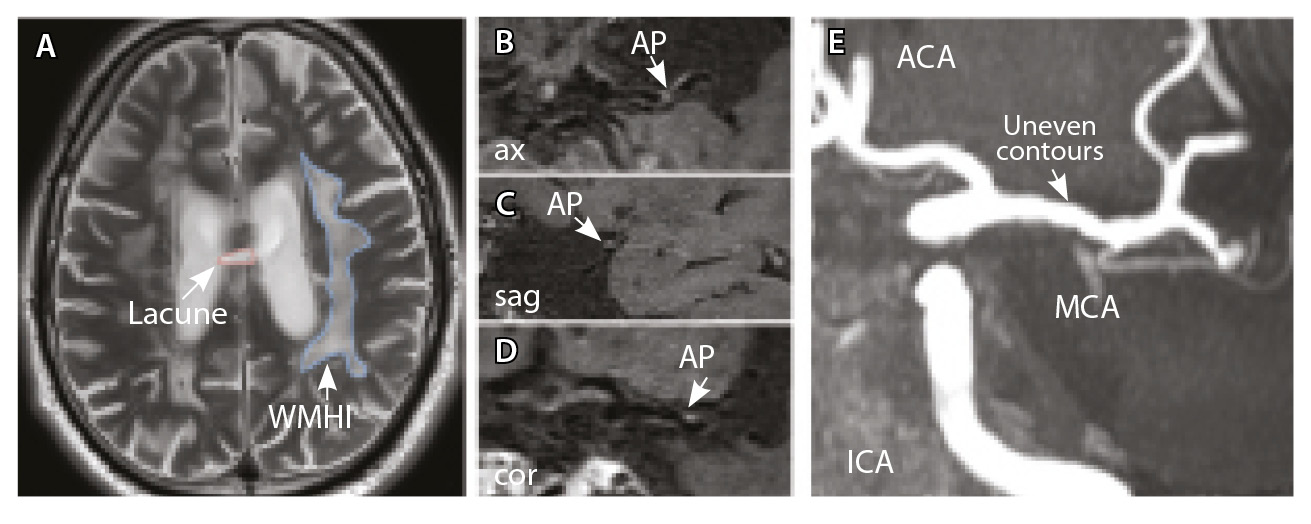

У всех включенных в исследование пациентов определялись атеросклеротические изменения брахиоцефальных артерий, в том числе на интракраниальном уровне, разной степени выраженности. У 9 больных отмечались признаки отрицательного ремоделирования артерий – выявление АСБ в стенке артерий, без сужения их просвета. Присутствовали изменения вещества головного мозга: инфаркты, в том числе лакунарные, – в 17 (58%) наблюдениях; МРТ-признаки церебральной микроангиопатии (ЦМА) – у 20 (68%) пациентов, среди них со степенью выраженности (F) по шкале Fazekas: F1 – у 7 (35%), F2 – у 4 (20%) (рис. 3), F3 – у 9 (45%) (рис. 4) [27]. Средние, большие и обширные инфаркты мозга зарегистрированы у 6 (20%) больных. Для количественной оценки изменений АСБ выбирался наиболее пораженный участок артерий (за исключением окклюзии): в 12 (41,4%) случаях это был интракраниальный сегмент внутренней сонной артерии (ВСА), в 10 (34,5%) – средней мозговой артерии (СМА), в 6 (20,7%) – базилярной артерии (БА), в 1 (3,4%) – задней мозговой артерии (ЗМА) (см. табл. 1).

Рис. 3. Пациент Ц., 53 года, с признаками церебральной микроангиопатии (F3 по шкале Fazekas), атеросклерозом интракраниальных артерий, без формирования гемодинамически значимых стенозов. А – магнитно-резонансная томография (МРТ) головного мозга, режим Т2-взвешенного изображения: видны обширные сливные зоны гиперинтенсивности белого вещества (ГИБВ) с наличием на этом фоне лакунарных инфарктов; Б, В, Г – МРТ сосудистой стенки, режим T1-TSE-db-FS после контрастного усиления: в сегменте М1 левой средней мозговой артерии (СМА) визуализируется эксцентричная атеросклеротическая бляшка (АСБ), интенсивно накапливающая контрастный препарат; Д – трехмерная магнитно-резонансная времяпролетная (3D ToF) ангиография: выявляется неровность контуров левой СМА в сегменте М1; ax – аксиальная, sag – сагиттальная, cor – коронарная плоскости; ВСА – внутренняя сонная артерия; ПМА – передняя мозговая артерия